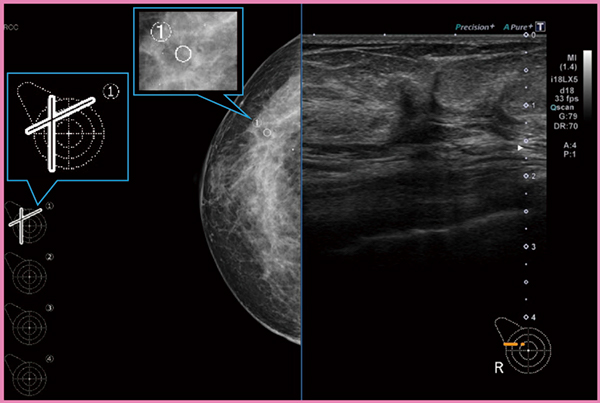

マンモグラフィ所見を参照しながら超音波検査を行う上で課題となるのは,両者の画像のオリエンテーションの違いであり,正しく位置を把握するためには検査者のスキルが必要になる。Aplio i-seriesで使用できるBreast Scan Guideは,超音波検査技師がマンモグラフィ画像上の病変位置を正しく把握し,超音波検査を行えるように支援するために開発された機能である。Aplio i-seriesでマンモグラフィ画像を読み込み,病変位置を登録すると,ボディマーク上に病変の推定位置が表示される。MLO像とCC像の2枚の画像で病変位置を登録すると2本の線が表示され,交点(←)が病変の推定位置を表す(図4)。本機能によって,マンモグラフィで病変が疑われる部位を超音波で検出しやすくなることが期待される。

図5は,マンモグラフィ画像と超音波画像の2画面表示である。画面左は右乳房のマンモグラフィCC像であり,マンモグラフィ画像上の(1)の位置とボディマーク上の推定位置とが対応している。このように,マンモグラフィ画像やボディマーク推定位置を参照しながら超音波検査を行うことができるため,マンモグラフィと超音波による総合判定を支援できると考えている。

図4 Breast Scan Guide

図5 マンモグラフィ画像と超音波画像の2画面表示

(画像提供:高松平和病院・何森亜由美先生)